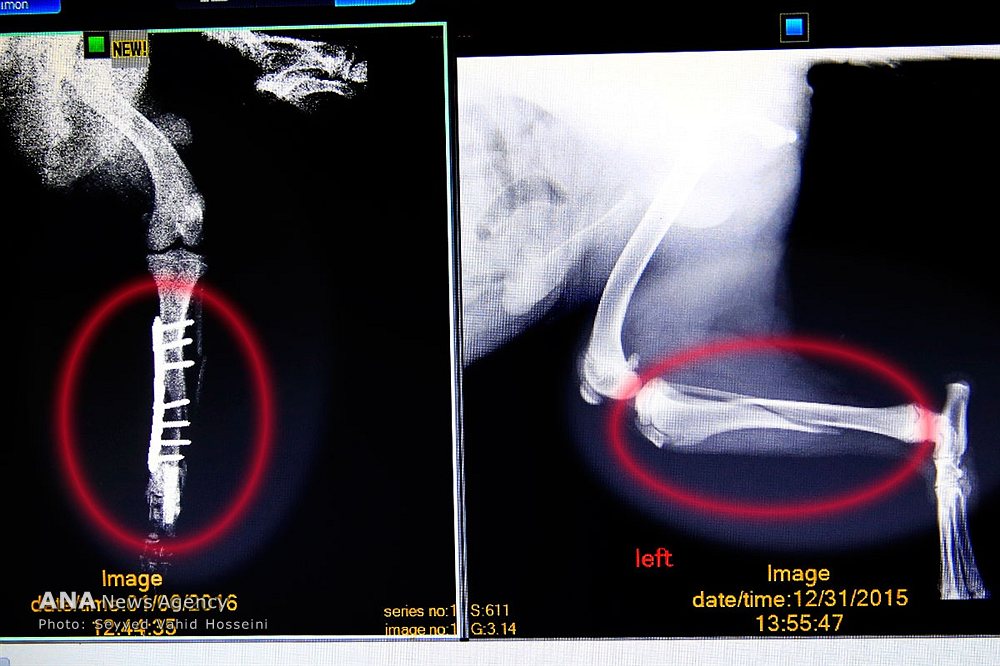

روایت تصویری خبرگزاری آنا از فعالیت دامپزشکان در بیمارستان دامپزشکی مرکزی (تصاویر)